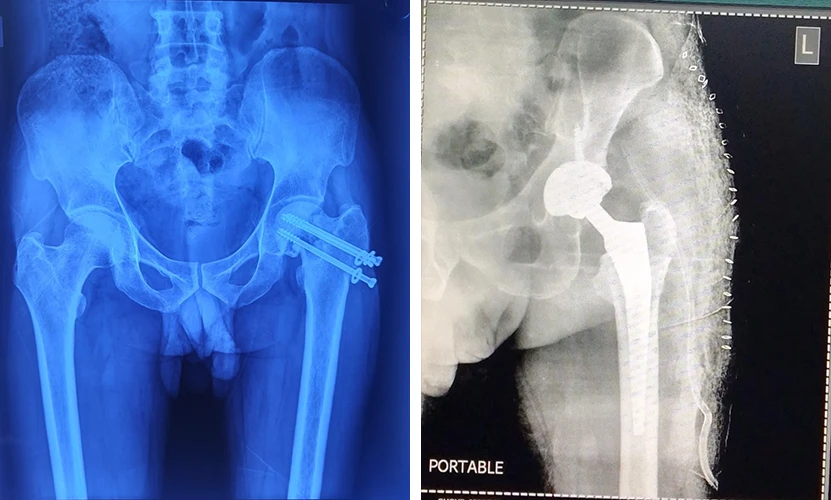

Total Hip Replacement

Are your hips causing you constant discomfort? If you're tired of living with hip pain, Dr. Prasun Sanyal is your best solution.

My mother had hip fracture in 2018. We consulted Dr. Sanyal through a recommendation from my neighbour. My mother was operated for Hip Replacement. Immediately after surgery she was allowed to stand.

Dr. Sanyal thoroughly followed up in post op & he was accessible for any query of us. My mother visited Kamakhya Temple in 2020 climbing all stairs. 5 years down She is absolutely fit & living a normal life. My heartfelt gratitude to Dr. Sanyal for his exceptional care & compassionate attitude

Siddhartha Basu

Dr Sanyal is a profoundly gentle and considerate doctor. I know little about orthopedic surgery. But the deep care simultaneous with confidence, he treated my mother with, I am truely pleased. And moreover, it the 22nd day after hip joint surgey, and in the total period of healing, my mother almost complained nothing about any post surgical pain. And last but not the least, Dr Prasun Sanyal is exceptionally communicable and easy to approach to the patients, a rare trait for a busy surgeon like him.

I really am and would remain thoroughly grateful to him. Thanks ডাক্তারবাবু।